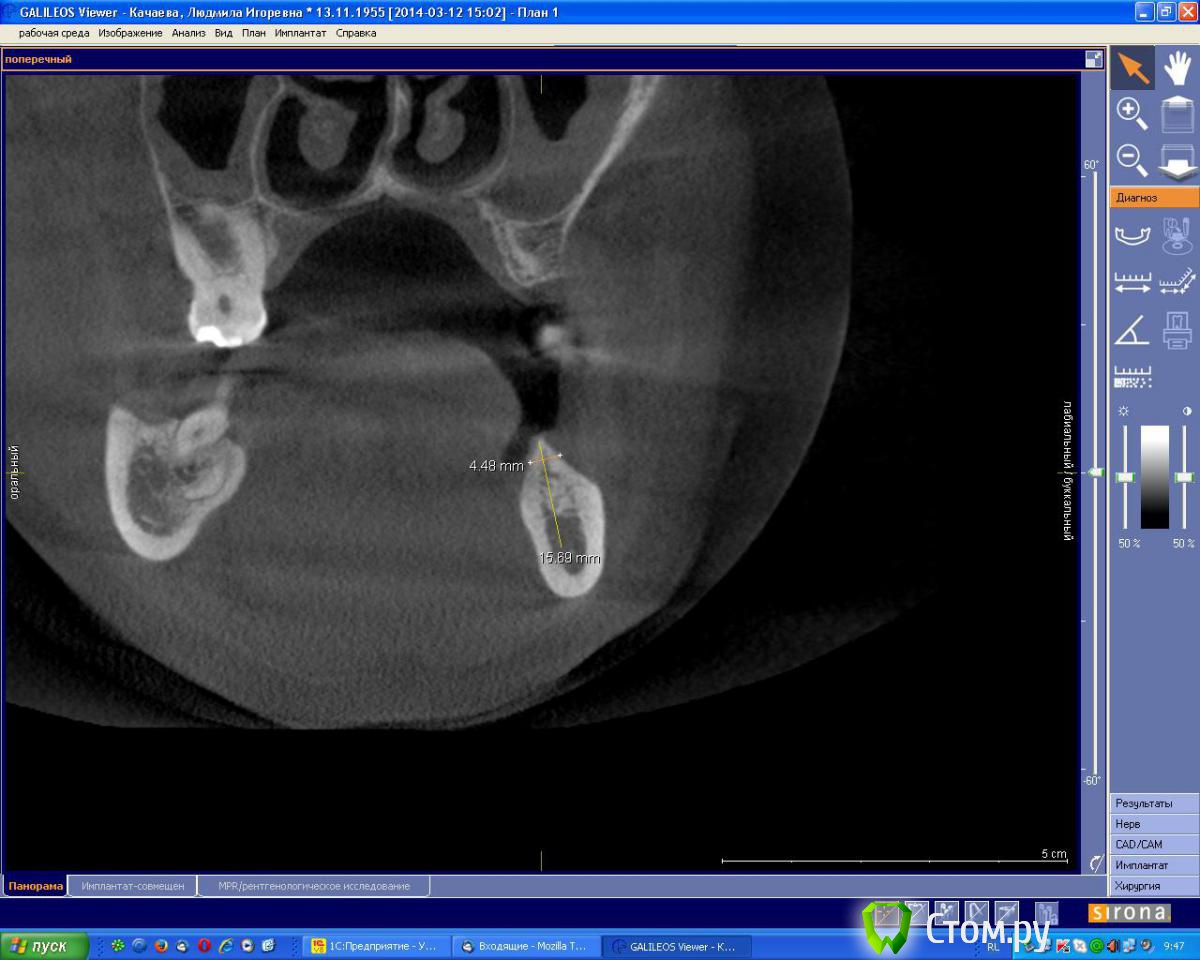

an_ver Опубликовано 7 августа, 2014 Поделиться Опубликовано 7 августа, 2014 Планируется установка 2 имплантов в обл.35,37 по высоте проходит,по толщине нет.Предпочтительный метод в данной ситуации? Ссылка на комментарий

Аслан Опубликовано 7 августа, 2014 Поделиться Опубликовано 7 августа, 2014 (изменено) Вот тут бы без сомнений просто поставил чуть поглубже и вестибулярно досыпал.Хотя можно и заморочиться и перевернуть блок, как показывал Эдуард. Изменено 7 августа, 2014 пользователем Аслан 4 Ссылка на комментарий

red_butler Опубликовано 7 августа, 2014 Поделиться Опубликовано 7 августа, 2014 ставить поглубже и НКР 1 Ссылка на комментарий

Mane Опубликовано 7 августа, 2014 Поделиться Опубликовано 7 августа, 2014 Задача - поставить болт так что по кругу своя кость получилась - или просто зуглибив или расщепление и перевернутый блок. Далее сразу НКРВозможно сразу с десной 2 Ссылка на комментарий